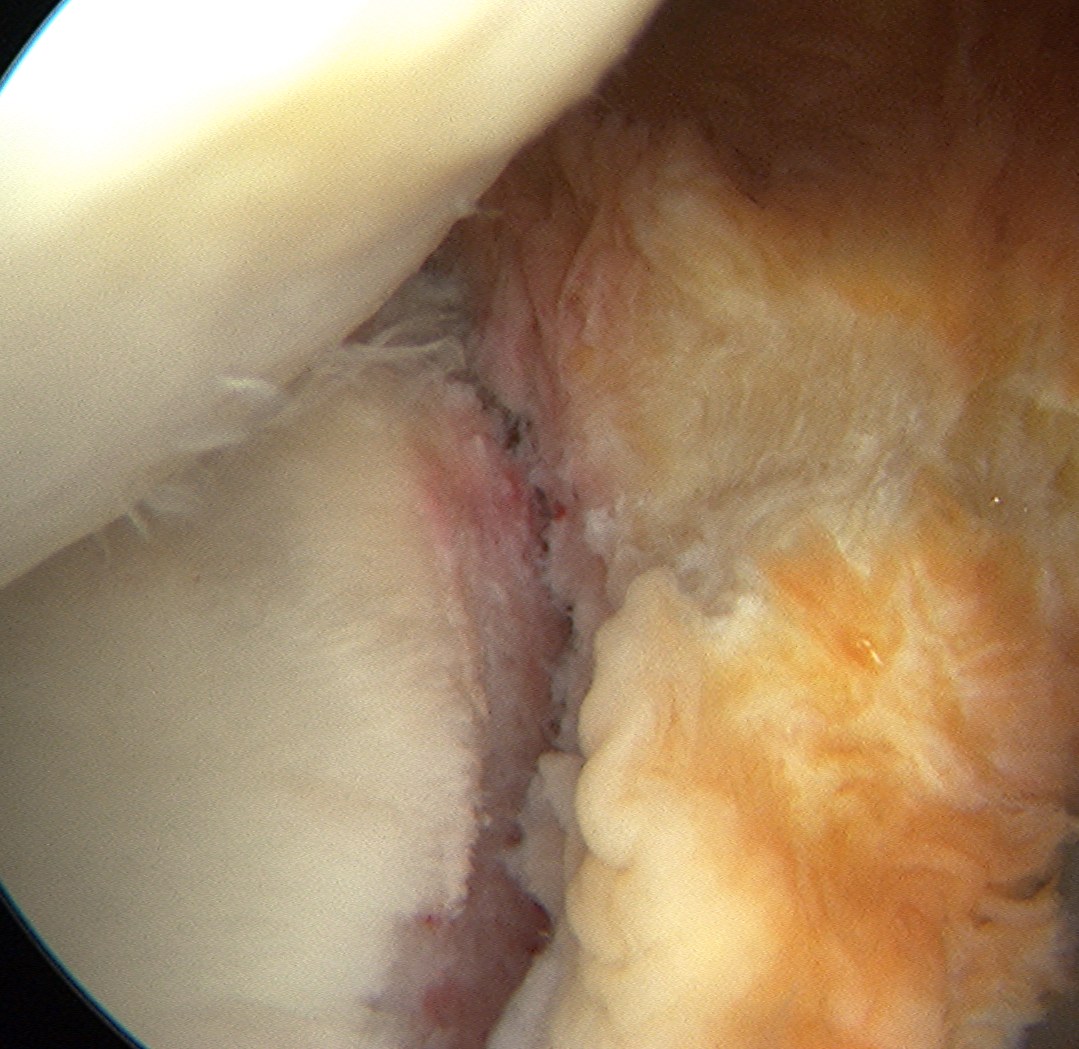

Technique arthroscopic anterior labral / Bankart repair

Steps

Mobilize anterior labrum

Debride anterior glenoid to bleeding bone

Debride anterior glenoid bone to bleeding bone

Insert anchors

Inferior anchor at 5.30 o'clock

- curved anchor guide / trans-subscapularis

- on rim of glenoid

Other anchors typically at 3 and 4 o'clock

Pass sutures and tie knots

Typically curved suture passers

Aim to tighten capsule medially and superiorly onto glenoid